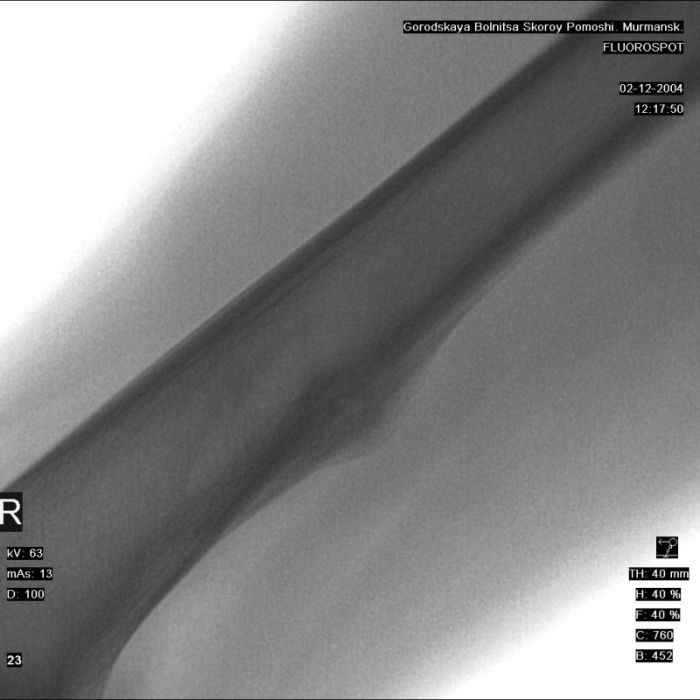

Анамнез практически никакой: в следствие травмы (растяжение связок коленного сустава) от 07.11.2004 выполнены Rg-граммы в травмпункте и обнаружено опухолевидное образование. Первичные Rg-граммы я не публикую, так как они заметно худшего качества, да и динамики за прошедшие три недели не отражают. Болевой синдром купирован в течение трёх дней. В настоящий момент мальчика ничего не беспокоит. Ходьба не нарушена, опухоль пальпируется с трудом по задней поверхности в н\3 правого бедра, пальпация безболезненна, объем движений в суставах правой нижней конечности полный и симметричный. Кожа над опухолью не изменена. В нашей клинике проведено дополнительное обследование: общие анализы крови и мочи, биохимия крови без особенностей. Выполнены Rg-граммы на цифровом Siemens обычные и продольные томограммы срезами 3-5 мм, а также компьютерная томография поперечными срезами по 5 мм. Прошу обратить внимание, что на приведённых томограммах видны две полости 10х15 мм и 15х60 мм. Также имеются два опухолевидных образований наслаивающихся друг на друга: уплощённое и вытянутое 10х100 мм и элипсовидной формы 15х30 мм. Это хорошо заметно на фото a_1.jpg c_1.jpg и d_1.jpg. Плотность внутри полостей 125% от плотности костномозгового канала, плотность наружного опухолевидного образования 55% от плотности кортикального слоя. Также отмечается линия перелома по центру наружного опухолевидного образования. Исходя из полученных данных мнения в плане диагноза несколько разделились от 1)сочетания кортикальной фиброзной дисплазии и латентно протекавшего маршевого перелома н\3 правого бедра до 2)остеосаркомы. В отношении первого варианта не сходится отсутствие клиники при переломе такой крупной кости как бедро, второй вариант вообще оставлю без комментария, ибо некомпетентен. Хотелось бы услышать мнения коллег, с удовольствием ознакомлюсь с любыми предположениями и замечаниями. С уважением, Александр Е. Клоков Отделение детской ортопедии и травматологии БСМП г. Мурманска.